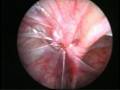

Can this operation done by laparoscopy?

Operation in hernia involves closing of the open passage through which the testis has come down. This can be done from outside as in open surgery or from inside by laparoscopy. If your child has got a hernia on one side, there is a 15 – 25 % chance that he / she may develop a hernia on the opposite side at a later date. With the help of laparoscopy we are able to look at the opposite side to see if the passage is open on that side as well. This can be closed at the same sitting if you wish to. Recovery from surgery, timing of surgery and discharge from hospital are the similar for open surgery and laparoscopic surgery.

However, it is important to note that an open passage does not always mean that your child will get a hernia. There is no harm in opting for a second surgery later if your child at all develops a hernia on the opposite side.

Laparoscopic repairs have a slightly higher chance of recurrence (i.e. the hernia coming back again) as compared to open hernias. You can discuss the pros and cons in details with your doctor when you come for consultation.